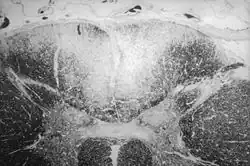

Drei bis fünf Jahre später sind nicht nur Eintrittspforte, Lymphknoten und Haut befallen. Die Erreger haben sich im ganzen Körper ausgebreitet und auch innere Organe wie Blutgefäßsystem, Atemtrakt, Rachen, Speiseröhre, Magen, Leber, Knochen und Muskeln befallen. Es bilden sich Knoten, die oft gummiartig verhärtet sind (Gummen oder Gummata, in der Einzahl [das] Gumma). Die Bezeichnung als „Gummi“ geht auf Girolamo Fracastoro zurück, der das Symptom der erweichenden Knoten in seinem Lehrgedicht über die Syphilis so benannte.[38] Histologisch stellen sich Gummen als monozytär-destruierende, plasmazellhaltige Granulome dar.[39] Sie treten insbesondere an Haut, Schleimhaut und Knochen auf. Auf der Haut bilden sie mitunter große Geschwüre, am Gaumen entsteht unter Umständen eine Perforation zur Nasenhöhle. Besonders gefährlich ist ein syphilitischer Knoten an der Hauptschlagader (Aorta), verursacht von einer Entzündung in der mittleren und äußeren Wandschicht derselben (Mesaortitis luetica). Etwa 30 Jahre nach der Infektion kann ein solcher Knoten als Spätkomplikation zu einer leicht aufreißbaren Aussackung der Aorta (Aortenaneurysma) führen. Sollte diese Ausbuchtung reißen, verblutet der Betroffene innerlich. Zudem kann auch das zentrale Nervensystem[40] befallen sein.